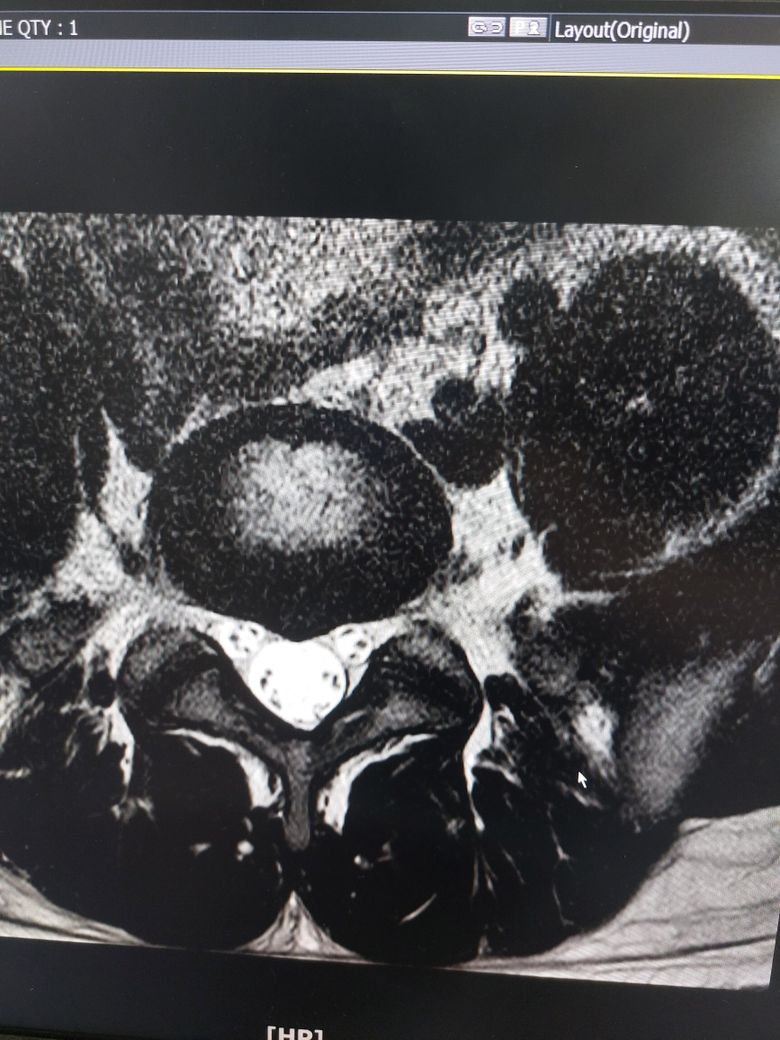

몇개월동안 요추부분이 뻣뻣하고 시큰거려서 (다리 증상은 없음) mri 촬영했는데

디스크 팽윤인가요 아니면 탈출인가요?

증상이 많이 심한가요?

추간판 팽윤입니다

MRI 영상만 가지고 말씀드린다면 심하지 않습니다.

• 올리신 사진 몇 장 가지고 정확한 상태 평가 및 판단을 내릴 수는 없지만 디스크 탈출 보다는 디스크 팽윤이 의심스런 MRI 소견으로 사료됩니다.